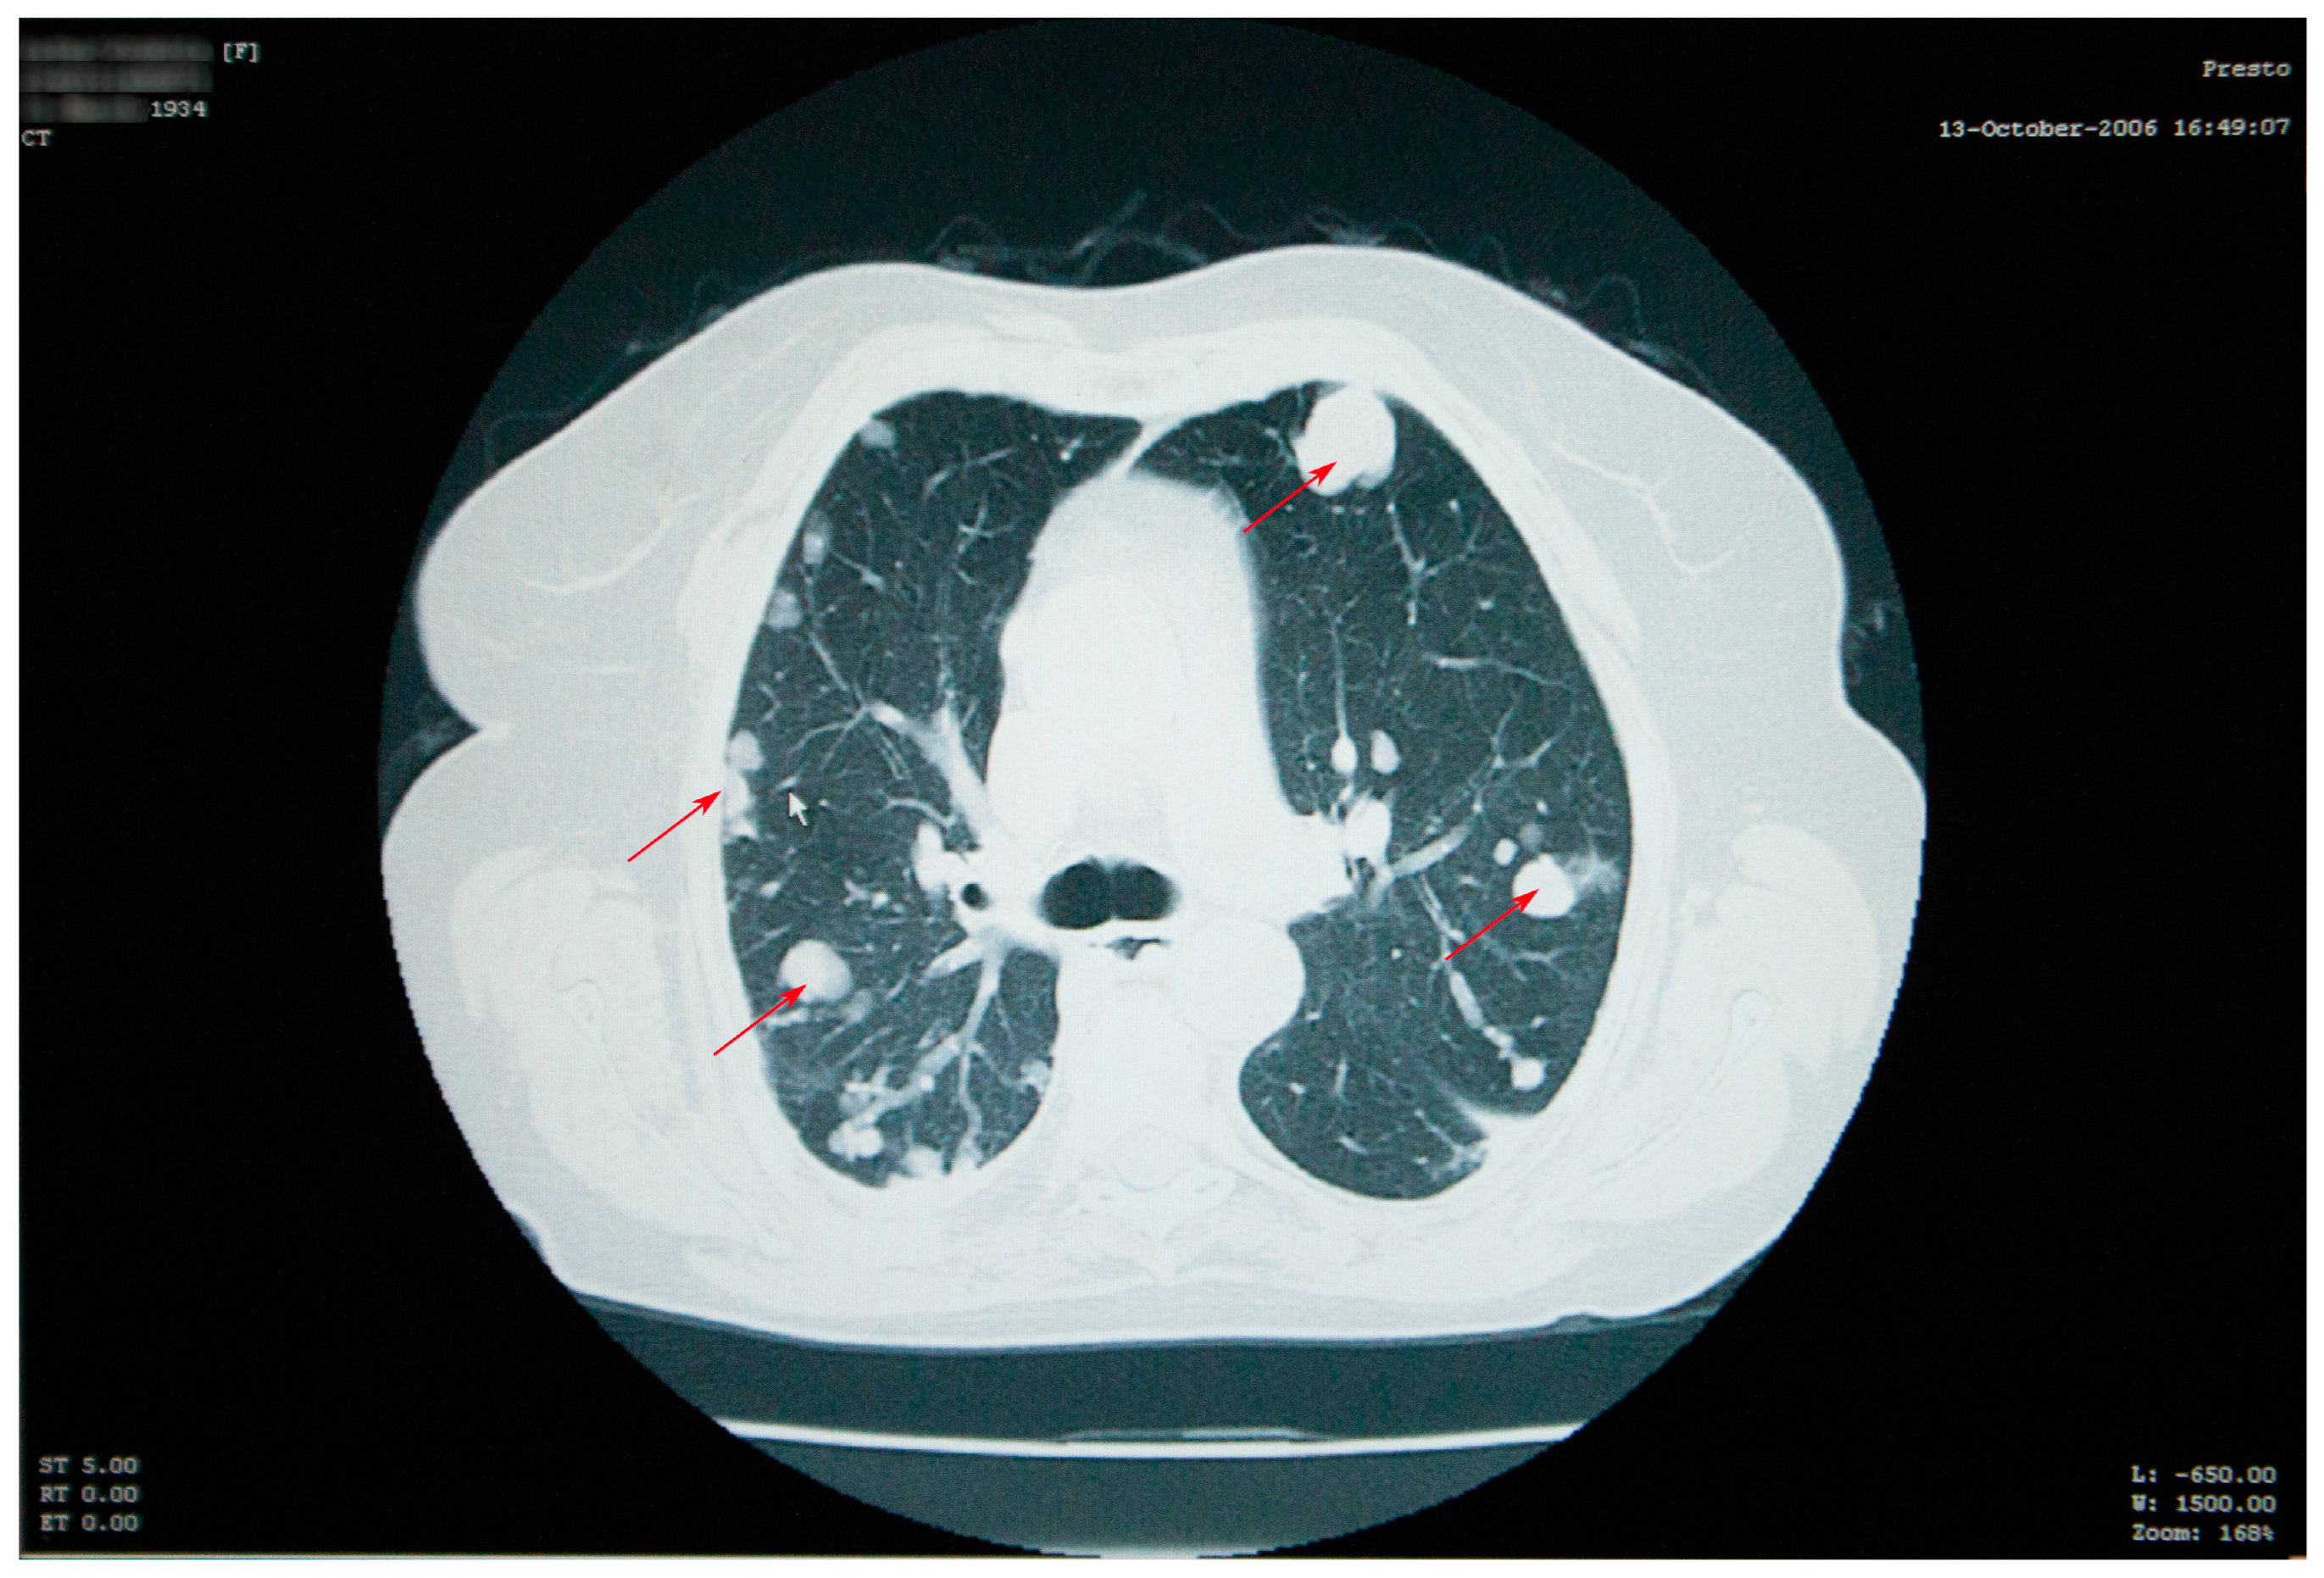

At her check-up in October 2006, the thoracic radiograph raised the suspicion of lung metastases from a cancer of unknown location (numerous 1–2 cm opacities, with bilateral lung dissemination) (Figure 1).

Thoracic and abdominal CT scans were performed, which revealed numerous thoracic masses, located in both the lungs and the pleura, round or oval in shape, centimetric or millimetric in size, with different consistencies, some liquid with calcifications, some condensed, sometimes clustering, as well as bilateral pachypleuritis, more pronounced on the right side (Figure 2).

Figure 2. Thoracic CT scan showing numerous thoracic masses (red arrows), located bilaterally, with different consistencies, and bilateral pachypleuritis.